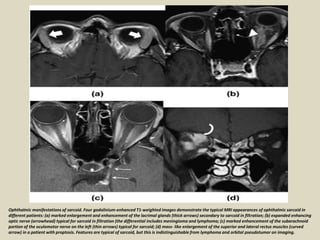

Ophthalmic manifestations of sarcoid. Four gadolinium-enhanced T1-weighted images demonstrate the typical MRI appearances of ophthalmic sarcoid in

different patients: (a) marked enlargement and enhancement of the lacrimal glands (thick arrows) secondary to sarcoid in filtration; (b) expanded enhancing

optic nerve (arrowhead) typical for sarcoid in filtration (the differential includes meningioma and lymphoma; (c) marked enhancement of the subarachnoid

portion of the oculomotor nerve on the left (thin arrows) typical for sarcoid; (d) mass- like enlargement of the superior and lateral rectus muscles (curved

arrow) in a patient with proptosis. Features are typical of sarcoid, but this is indistinguishable from lymphoma and orbital pseudotumor on imaging.